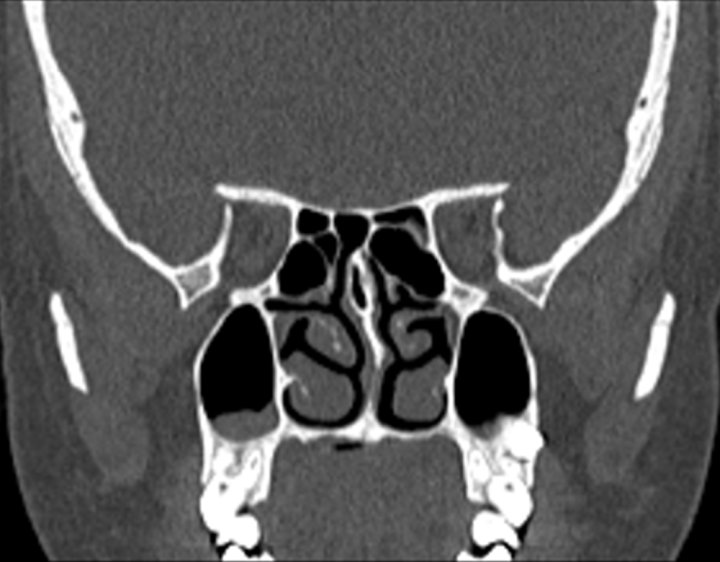

Click any image for labels.